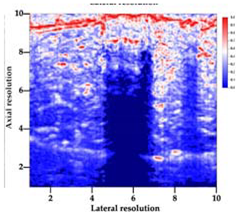

3.3. B-Mode Images

3.5. Echogenicity

4.1. Ultrasonography and Aerogel Dimensional Analyis

| Aerogel Type | US Image | Normalized Intensity Map | 3D Intensity Map | |

|---|---|---|---|---|

| 1 | Muscle |  |  |  |

| 2 | X-silica |  |  |  |

| 3 | X-silica-La2O2S:Eu |  |  |  |

| 4 | SMPU-Mix-14 |  |  |  |

| 5 | SMPU-Mix-18 |  |  |  |

| 6 | BRF-CA |  |  |  |

| 7 | ARF-CA |  |  |  |

| 8 | X-Ca-Alg-2 |  |  |  |

| 9 | X-Ca-Alg-1 |  |  |  |